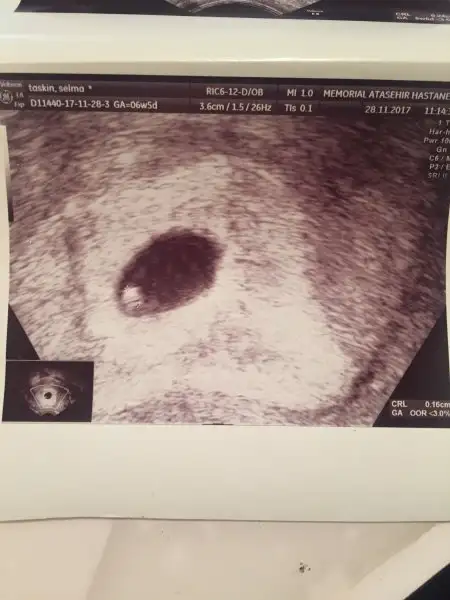

Eki Görüntüle 2075154 6 haftalık vajinal ultrason Ramzi teorisine göre kız sanırım ama vajinal olunca değişiyormuş